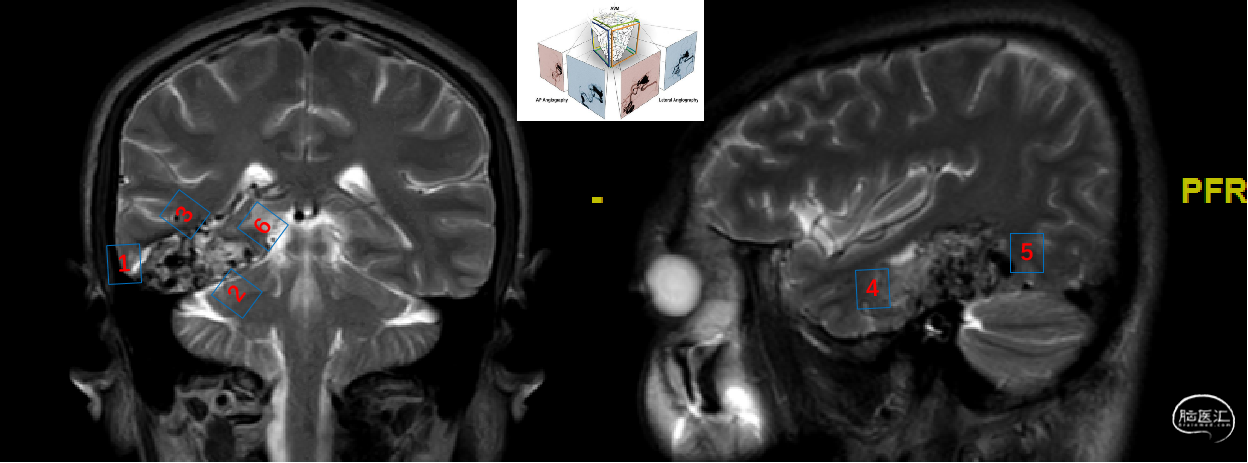

术前MRI

理解AVM六面体结构

深刻理解AVM畸形团“六面体”构造。该患者颞叶底面(颈外动脉硬膜支供血),颞下回外侧面(薄层脑组织)属于易于显露和控制的界面。